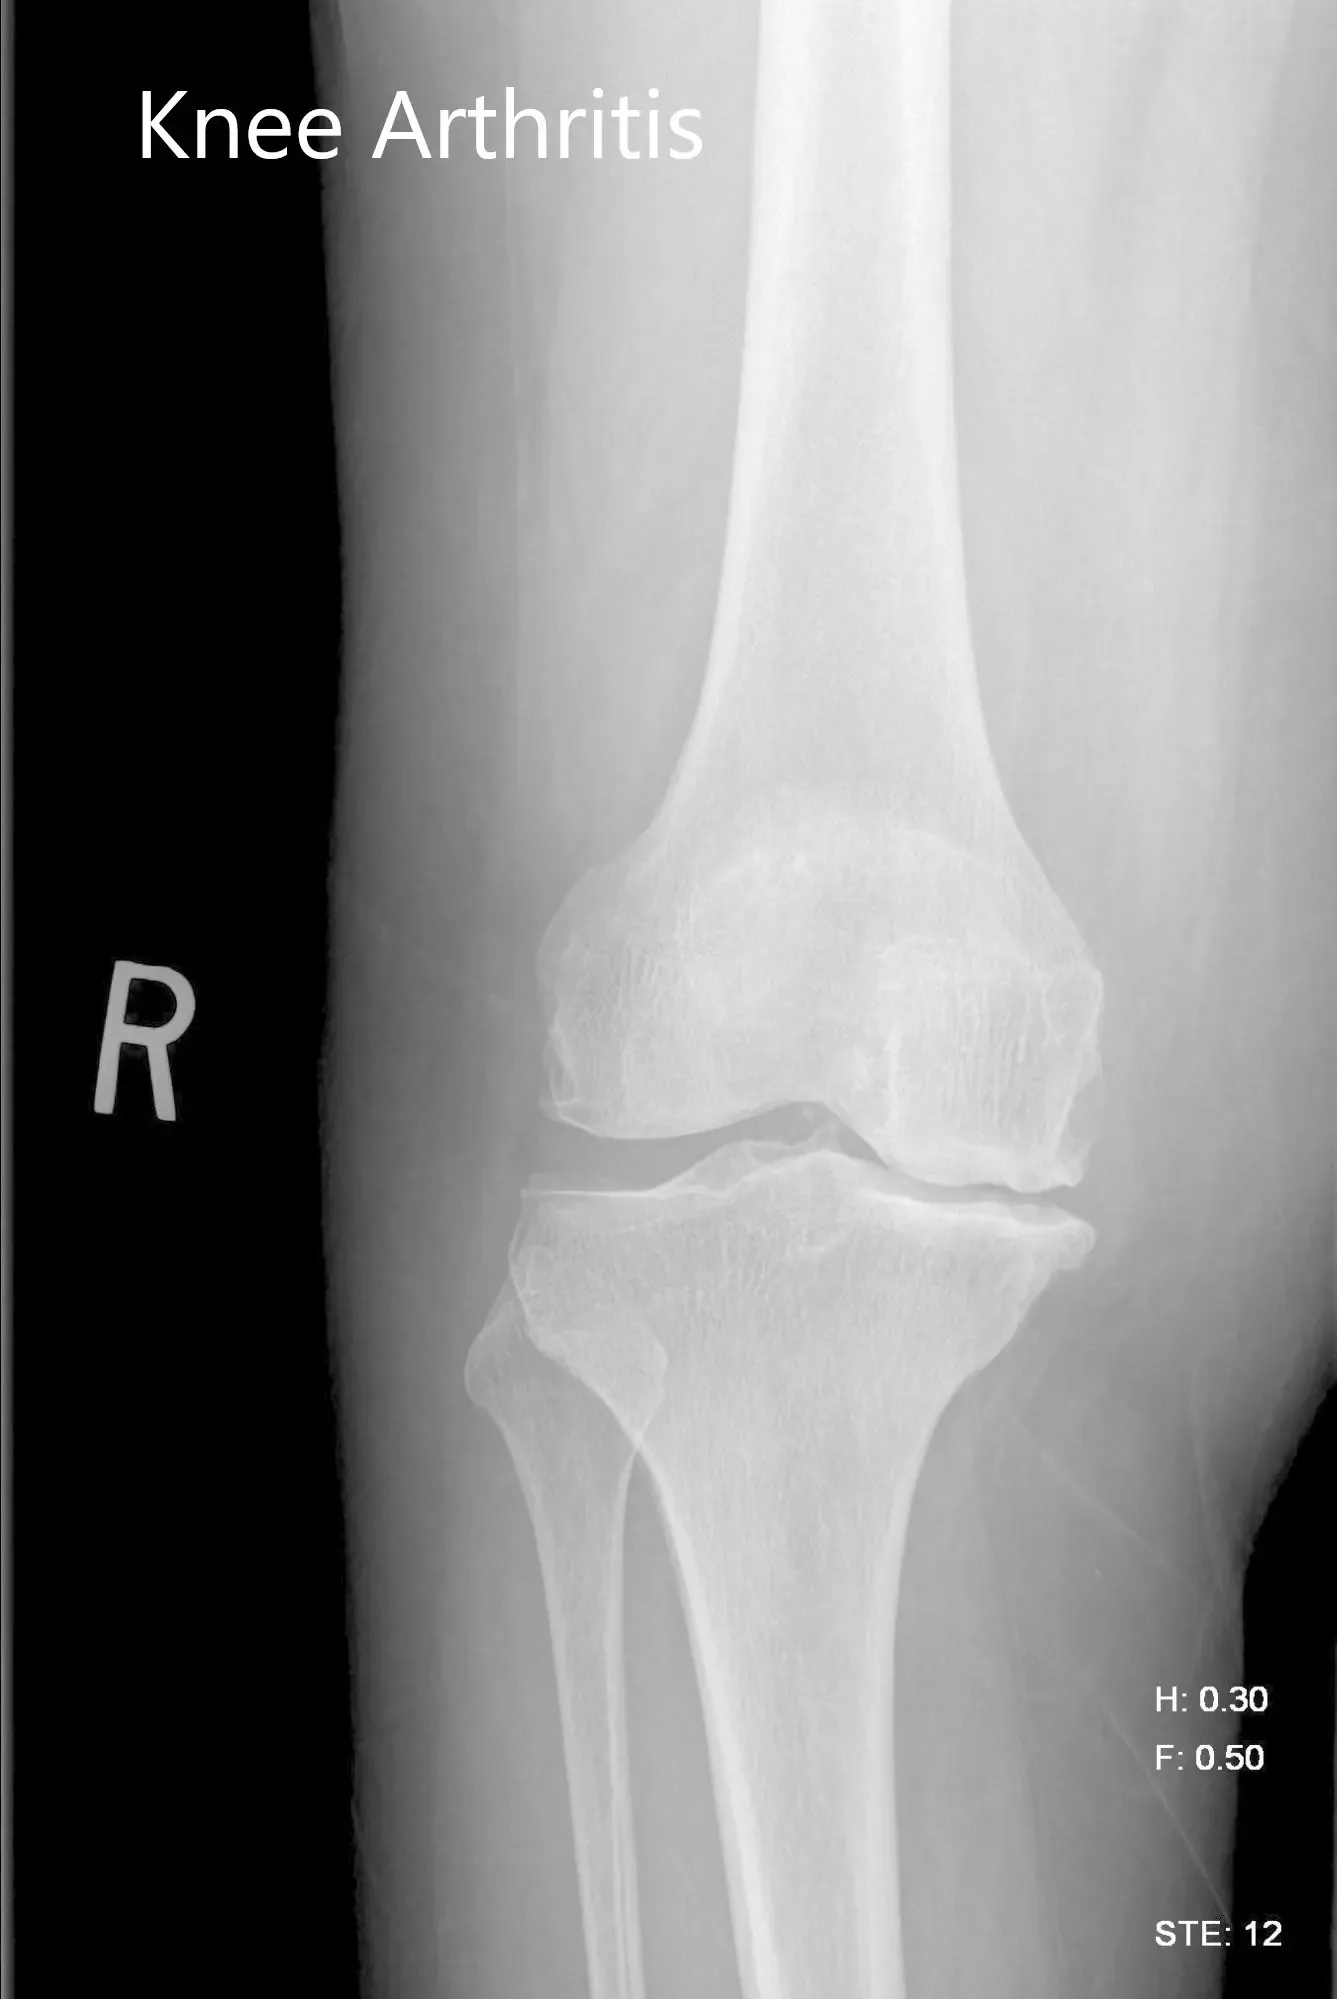

Imaging studies were obtained revealing tricompartmental osteoarthritis of the right knee with severe involvement of the medial compartment. Considering the patient’s condition and demands, he was deemed as a candidate for total knee replacement with custom implants. Other treatment options including nonsurgical methods were discussed in detail with him. He agreed for a custom right knee replacement.

Preoperative X-ray image of the right knee showing AP and lateral views